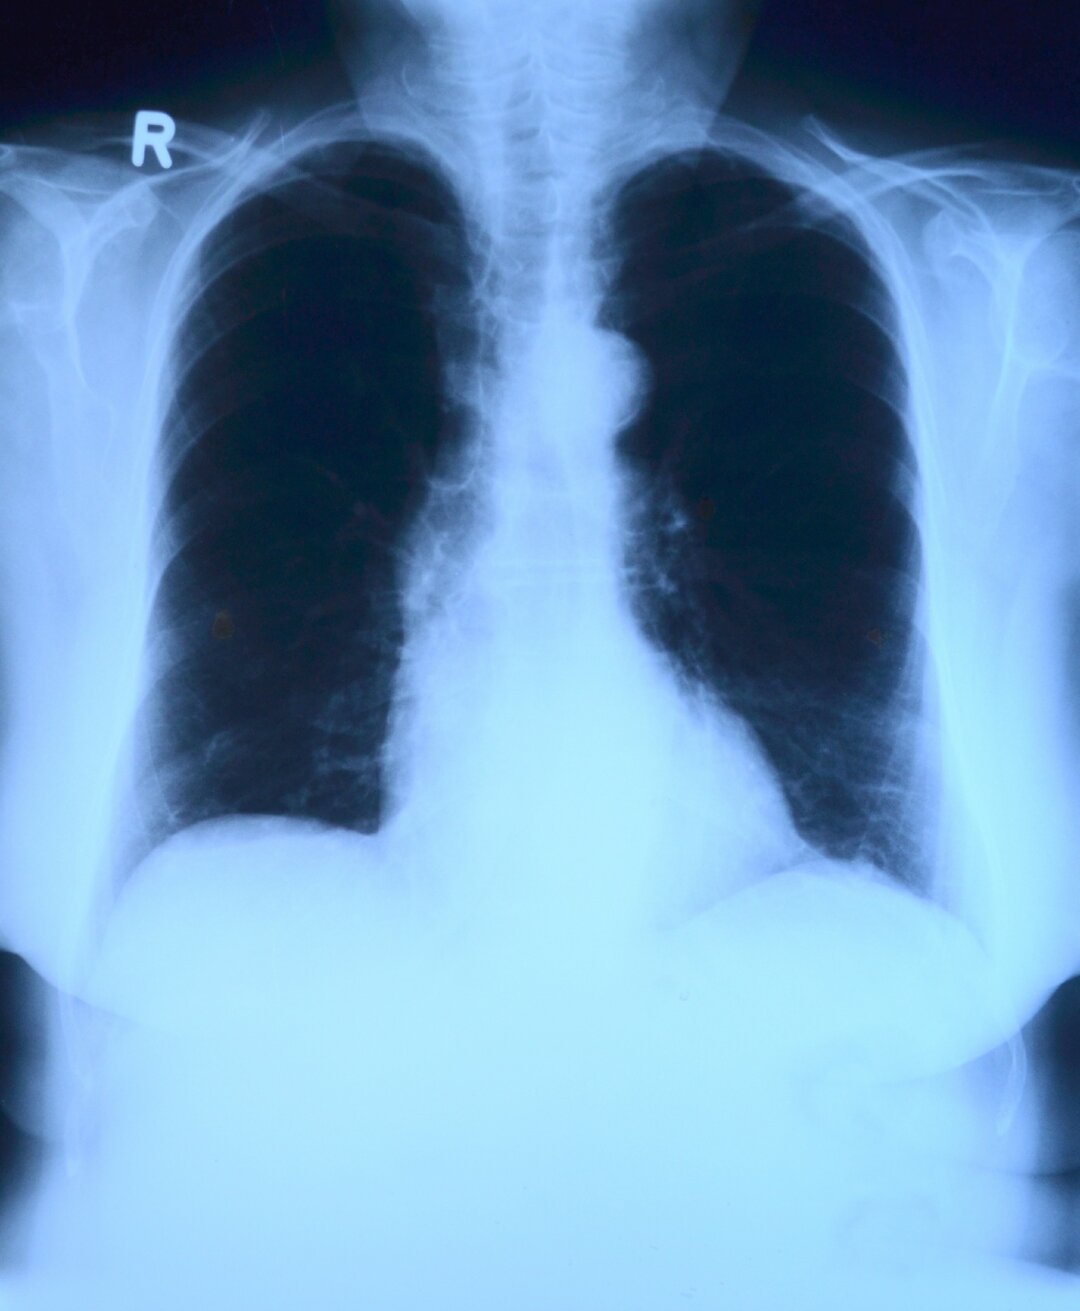

Если раньше флюорографическое исследование проводилось методом двойного чтения, чтобы исключить ошибки в скрининге, и флюорографический снимок смотрели два врача, то сейчас используется третье мнение – это мнение искусственного интеллекта. Сотрудники Областной туберкулезной больницы были одними из первых, кто начал применять эту технологию на практике.

«Искусственный интеллект анализирует флюрограммы, мамограммы и компьютерные томограммы, включая малодозные, – рассказала заведующая рентгенологическим отделением Ольга Лелянова. – Он видит очаговое образование, пневмоторакс, патологию плевры, патологию корня легкого и все это дело подчеркивает. Это облегчает работу, потому что открывая вот это «третье мнение», врач сразу видит, на что обратить дополнительное внимание. Это страхует нас от пропуска патологии, потому что позволяет дополнительно, так сказать, зацепиться, акцентирует наше внимание на каких-то патологических изменениях. Или изменениях, которые могут быть патологическими».

Компьютерный анализ снимков ускоряет диагностику, особенно при проведении массовых скринингов. Если же мнение специалиста и программы расходятся, то итоговое решение принимает врач. Система только заостряет внимание на отклонениях от нормы, а специалист решает, что это: погрешность из-за неправильной позы пациента, суммация теней или все же патологическое состояние.

В тестовом режиме система искуственного интеллекта запущена полтора года назад, в «боевом» работает уже год. Все снимки, которые выполнены в цифровом формате, проходят через нее. По словам Ольги Леляновой, к банку данных и системе анализа подключены почти все городские поликлиники и крупные больницы, тогда как в частном секторе врачи работают без поддержики искусственного интеллекта.